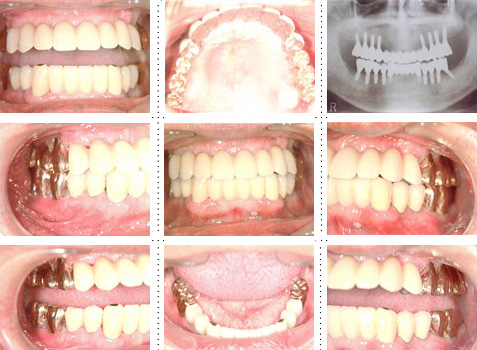

症例11

57才 女性

5年前に上顎に5本インプラントを埋入し、金属の冠をセットしました。インプラント部は快適に使用していたのですが、上顎の他の部位と下顎臼歯部のインプラントの治療を希望し来院。インプラント患者さんのリピーターが増加しております。

下顎は6本のインプラント埋入し冠をセット。上顎残存歯は将来を考え全て抜歯。4本のインプラントを追加埋入し、全顎ブリッジをセット。この様なケースが増えています。

以前のインプラントはそのまま使用可能で冠だけをやり直す事になります。